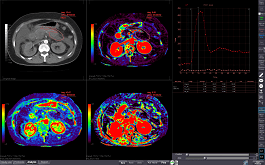

Analyzes blood flow using contrasted CT images as volume data scanned at the same cross-section or VR aspect, showing changes over time.

Analyzes blood flow using contrasted CT images scanned at the same cross-section, showing changes over time.